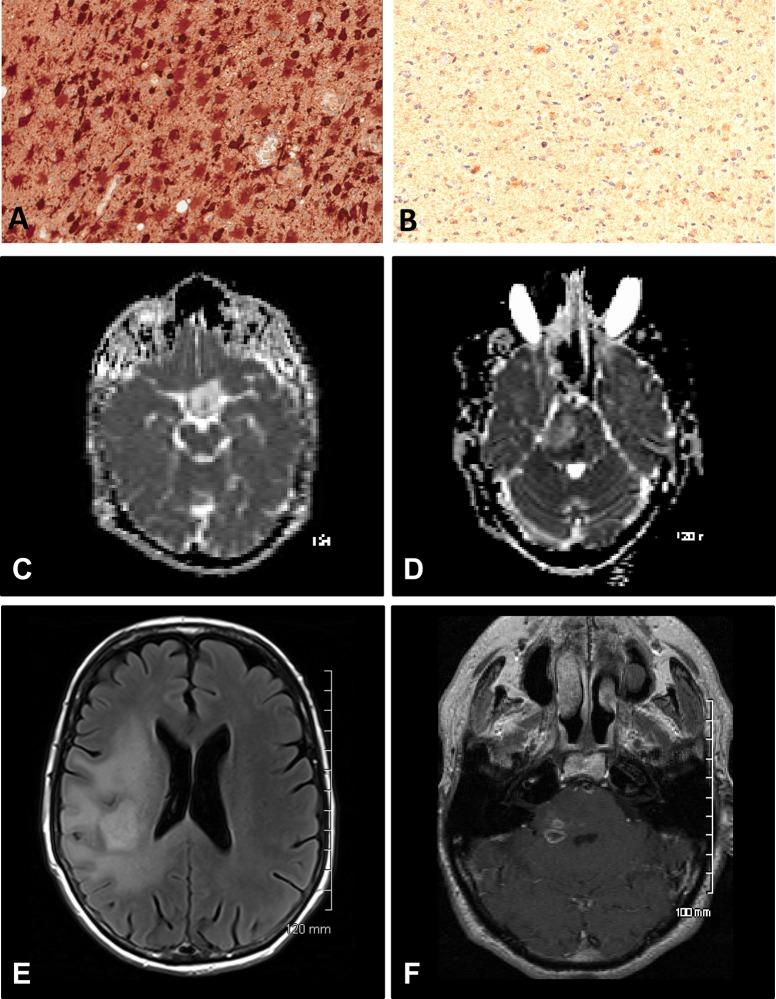

Radiological and pathological features associated with IDH1-R132H mutation status and early mortality in newly diagnosed anaplastic astrocytic tumours.

37 gliomas were studied; 18 were positive for the IDH1-R132H mutation. No tumours demonstrated a combined loss of chromosomes 1p/19q. Patients with IDH1-R132H-positive tumours were less likely to die within 12 months of diagnosis (17% vs. 47%; p=0.046), more likely to have tumours located in the frontal lobe (55% vs. 16%; p=0.015), and have a higher minimum apparent diffusion coefficient (1.115 x 10-3 mm2/sec vs. 0.838 x 10-3 mm2/sec; p=0.016), however, these variables demonstrated only moderate strength for predicting the IDH1-R132H mutation status (AUC=0.735 and 0.711, respectively). The Ki-67 index was significantly lower in IDH1-R132H-positive tumours (0.13 vs. 0.21; p=0.034). An increased risk of death was associated with contrast-enhancement ≥ 5 cm3 in patients with IDH1-R132H-positive tumours while edema ≥ 1 cm beyond the tumour margin and < 5 mitoses/mm2 were associated with an increased risk of death in patients with IDH1-R132H-negative tumours.